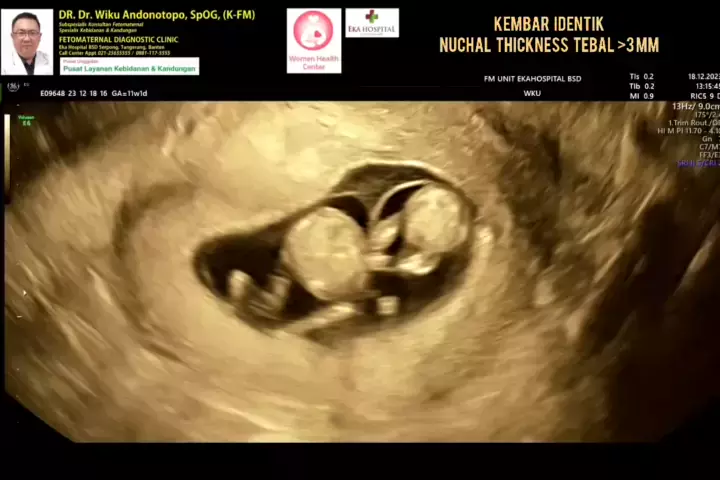

Kehamilan identik Kembar dgn kecurigaan kelainan genetika.... #fetomaternalcibubur #fetomaternalcirebon #fetomaternalsemarang #fetomaternalsolo #fetomaternaljogja #fetomaternalsurabaya #fetomaternalpurwokerto #usgfetomaternalekahospitalbsd #konsultanfetomaternalekahospitalbsd # #viral #indonesia #viral #indonesia # s # # #fetomaternalbalikpapan #fetomaternalbanjarmasin #fetomaternalbogor